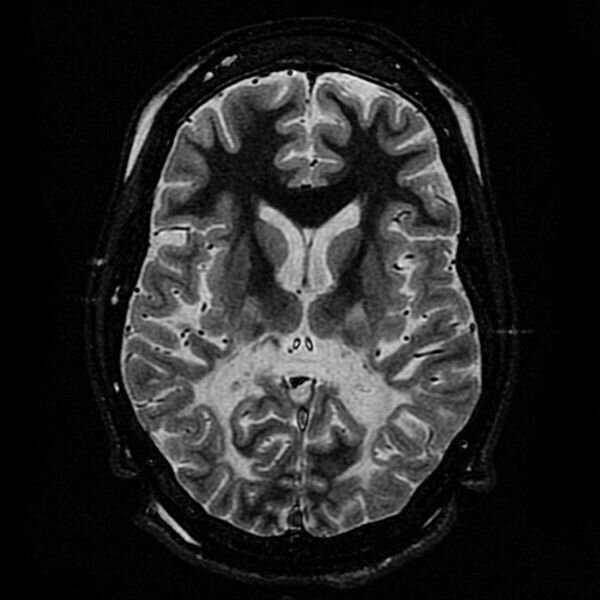

Внутрицеребральное кровотечение (ICH) имеет высокую заболеваемость и смертность во всем мире. Моторный дефицит, вызванный повреждением белого вещества (WMI), является одним из наиболее серьезных осложнений, ухудшающих качество жизни и может быть использован в качестве предиктора прогноза у пациентов с ICH.  ICH чаще всего встречается в базальных ганглиях и повреждает местные участки проведения белого вещества, в основном кортикально-спинального тракт. После кровоизлияния в базальные ганглии у пациентов наблюдаются очевидные гемиплегические симптомы из-за уменьшения силы контралатеральных мышц, а моторная дисфункция является основным прогностическим показателем. У пациентов сила мышц контралатеральной конечности может быть определена непосредственно с помощью инструкций. Однако большинство существующих методов оценки внутримозгового кровотечения у мышей напрямую связано с церебральной ишемией и отсутствием оценки двигательной дисфункции, вызванной разрушением белого вещества в базальн

ICH чаще всего встречается в базальных ганглиях и повреждает местные участки проведения белого вещества, в основном кортикально-спинального тракт. После кровоизлияния в базальные ганглии у пациентов наблюдаются очевидные гемиплегические симптомы из-за уменьшения силы контралатеральных мышц, а моторная дисфункция является основным прогностическим показателем.

Патологический процесс повреждения белого вещества в основном сопровождается повреждением и восстановлением кортикально-спинального тракта (CST), который тесно связан с двигательной функцией после кровотечения в мозгу.

В нормальных условиях, нетронутый миелин поддерживает трансдукцию CST и аксоновую функцию. При наступлении ICH обратимая патология CST включает демиелинизацию и отеки.

Ответы микроглии и астроцитов могут вызвать повреждение белого вещества, окружающего гематому, воспалением в острой фазе с 1-го по 7-й день после ICH.